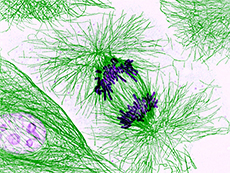

DINO RNA Molecule Triggers Anticancer Response in Damaged Cells

Studies in cells and mice found that, in cells with damaged DNA, a noncoding RNA called DINO stabilizes the p53 protein and guides the cells into cell death, preventing tumor development.